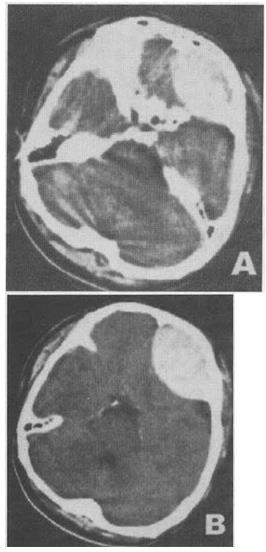

- 单项选择题 男性,42岁。被汽车撞伤1小时,昏迷状态。急诊CT检查如图像所示,诊断最可能是()。

A、脑实质出血

B、脑挫裂伤

C、硬膜下血肿

D、硬膜外血肿

E、蛛网膜下隙出血

- D